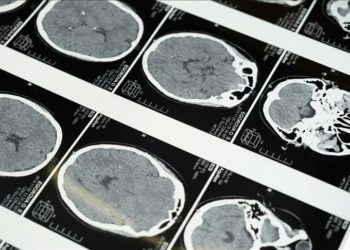

DetayAnkara'da uykuda dilini ısırma, dişlerini sıkma ve baş ağrısıyla gelişen sara nöbetleri şikayetleriyle hastaneye giden 47 yaşındaki Ali Gümüş'ün beyninde...